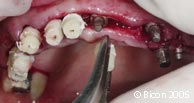

翻瓣。 |

![]() |